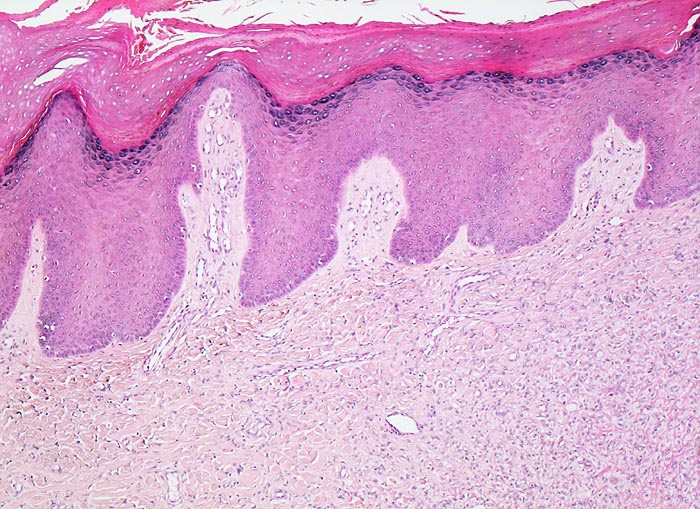

Benignes fibröses Histiozytom

Haut, obere Extremität

Die Epidermis über dem unscharf begrenzten dermalen Tumor ist hyperplastisch. Die Reteleisten sind verlängert. Es besteht ausserdem eine leichte Hyperkeratose. Intradermal findet sich ein mässig dichtes, unscharf begrenztes Tumorzellinfiltrat, welches die Kollagenfasern aufsplittert.

Auf Schnitt durch das Hautexzisat ist ein gelber unscharf begrenzter intradermaler Knoten erkennbar.

Derber indolenter rotbrauner Knoten am Arm, Durchmesser des Knotens 5mm.

50